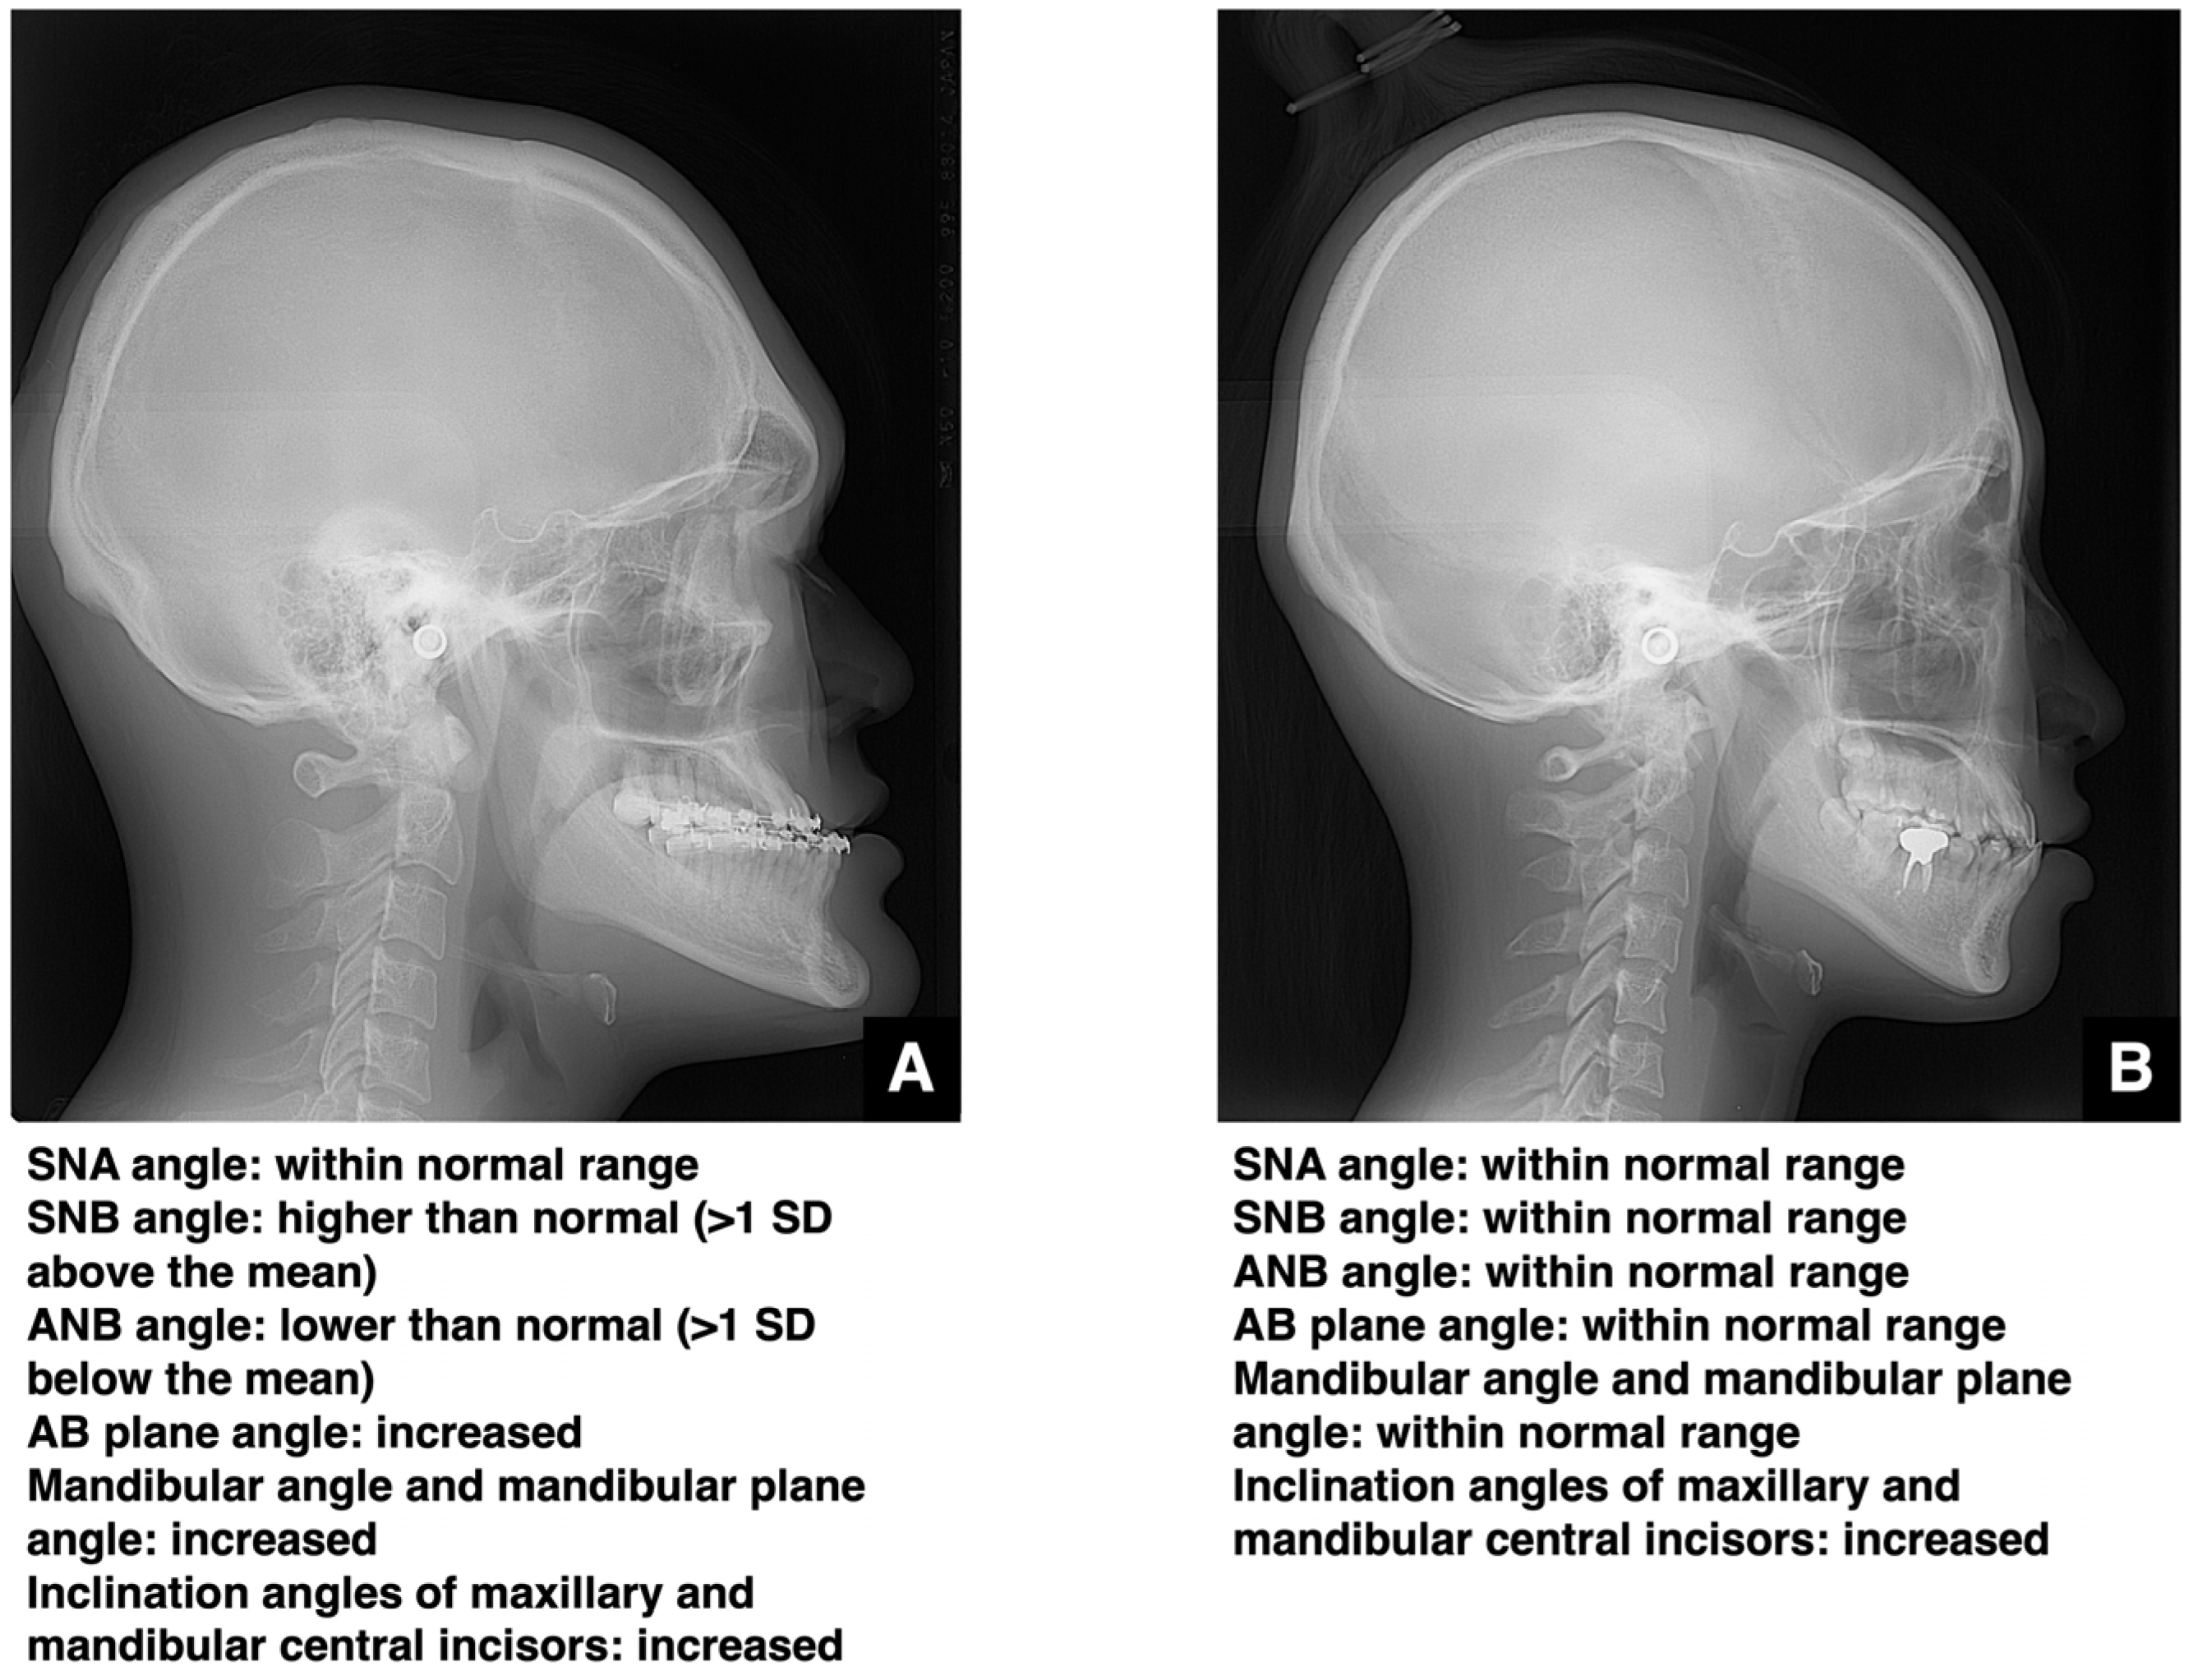

Types of Malocclusion

Causes of Malocclusion